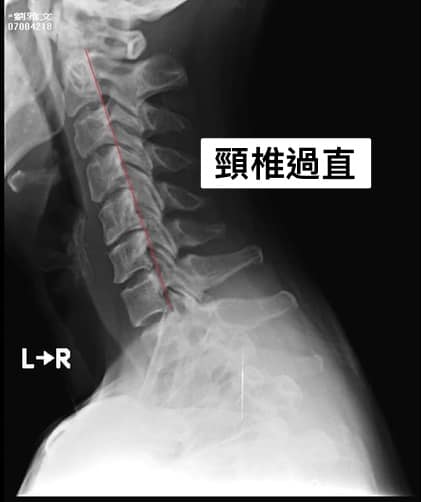

「夜半痛不成眠,甚至到了騎摩托車手麻到無法握住車把,這實在是很恐怖的事情」劉小姐回憶頸椎疼痛的這一年的故事,拍攝的X光片也接受了四個多月的復健,狀況時候時好時壞,一直到有一天發生上述事情才讓她驚覺她的頸椎出大問題,在門診當天我們立即幫她安排MRI,證實X光的懷疑真的是椎間盤突出,因為劉小姐的握力有一點點下降,團隊建議她先接受三周的治療,如果沒有看到效果則優先考慮神經外科諮詢或者開刀。

❇️診斷:C4/C5/C6壓迫神經根